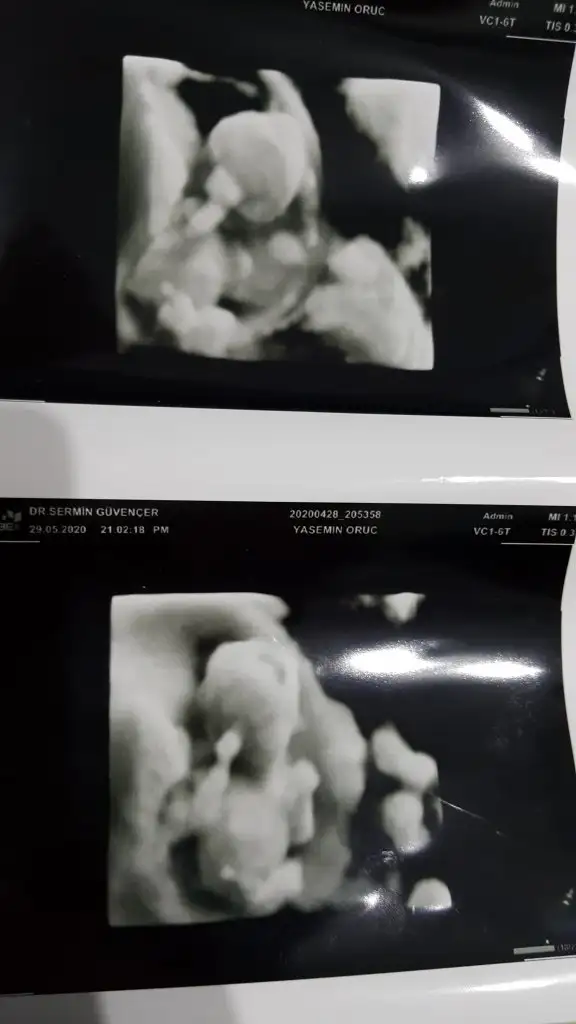

dr soylemeden siz gorun genital nub teorisi ( bebegin cinsiyeti)

Rica etsem banada tahmin yaparmisiniz 8 haftada kiz demistiniz tekrar gondermemi istemistiniz dayanamadim bu usg 11 haftalik

Kız gibi net de değil kız sanki 12-13 olunca tekrar usg paylaşın